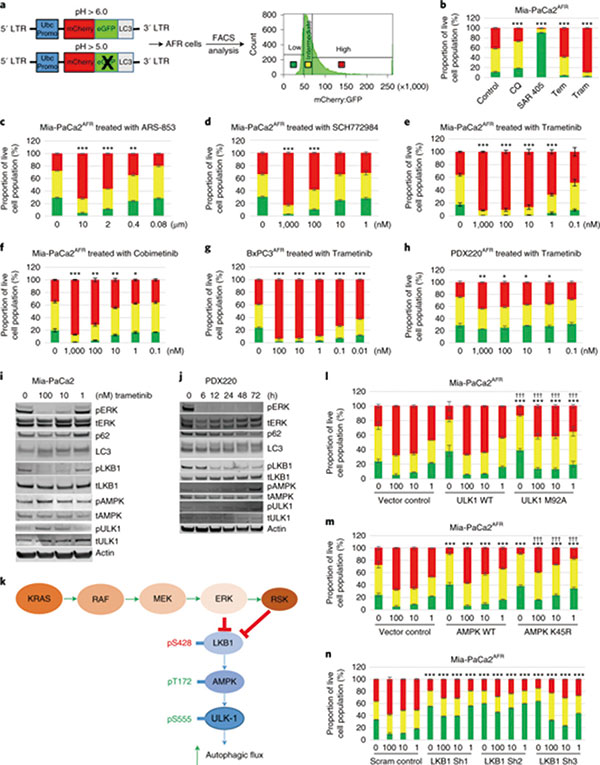

犹他大学附属亨斯迈癌症研究所收治的1例复发胰腺癌患者,无药可用的情况下,征得患者同意,研究者给予曲美替尼+羟氯喹治疗,患者腹部癌痛消失,肿瘤标志物CA19-9水平两个月内下降95%,治疗4个月CT显示,患者肿瘤负荷减少一半,只出现了轻微的皮疹和疲劳。